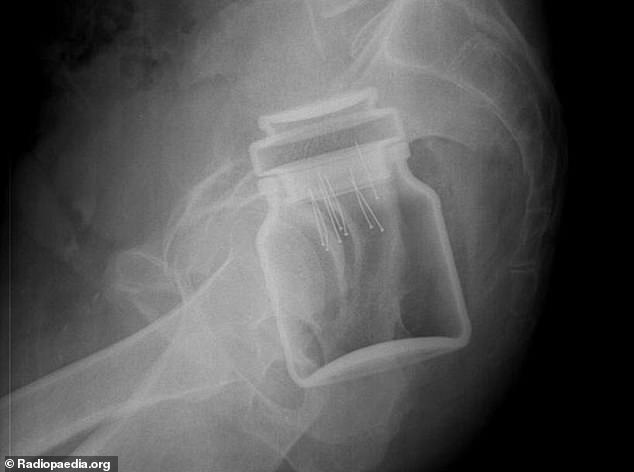

6. Ένα βαζάκι από αυτά που βάζουμε καφέ